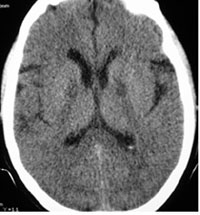

A 54-year-old man was brought to our hospital three hours after ingestion of 900 mg of chlordiazepoxide in a suicide attempt. Lab data’s revealed: acidosis with no abnormal glucose or electrolytes level. Brain CT scan showed diffuse massive supratentorial cytotoxic edema with sparing of infratentorial region (Figs. 4a-4c).

Diffuse massive supratentorial cytotoxic edema with sparing of infratentorial region in chlordiazepoxide overdose.